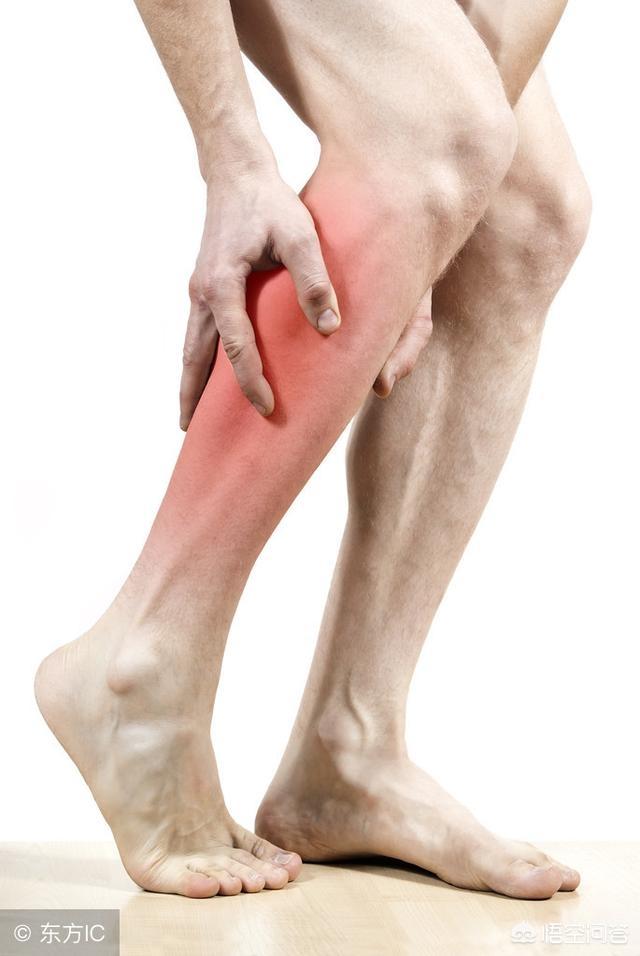

2.症状的には、腰部筋緊張はほとんどが腰部に限定され、片側発症または両側発症の可能性があり、ほとんどの痛みは我慢できる。腰椎椎間板ヘルニアは、痛みは激しく、活動は著しく制限され、臀部や脚に放散することもある。

3.身体徴候では、腰部筋緊張は腰部筋に明らかな固定圧迫痛があるが、放散痛はない。腰椎椎間板ヘルニアは腰椎深部の打診痛、下肢筋力低下、放散痛がある。

腰椎椎間板ヘルニア:腰仙部から坐骨神経の走行に沿って下肢に放散痛があり、四肢のしびれや重症例では間欠性跛行を伴う。ツボは背中の中央に位置することが多い。痛みは通常漠然としている。

腰痛に加えて、腰椎椎間板ヘルニアは坐骨神経の侵襲によって脚の痛みも引き起こしやすい。その痛みにはいくつかの特徴がある:

- 通常、腰痛は脚の痛みより先に起こるが、両方が同時に起こることもある;

- 椎間板ヘルニアの患部の棘突起に隣接するツボは限られている;

- 痛みは坐骨神経に沿って腰部からふくらはぎ外側、足背、足指に放散し、腰部4神経根が圧迫されている場合は大腿前面への放散痛も生じる;

- 脳脊髄液圧の上昇により、咳、くしゃみ、排便時に疼痛症状が増悪する;

- 痛みは活動時に強く、安静にしていると軽減し、腰が寒さや湿気にさらされると症状が悪化する傾向がある;

- 痛みだけでなく、腰や脚のしびれや痛みも一般的な症状である。

お尻や太ももの裏側、ふくらはぎの外側、時にはかかとまで痛むことがあり、くしゃみや咳をすると痛みが悪化することが多い。